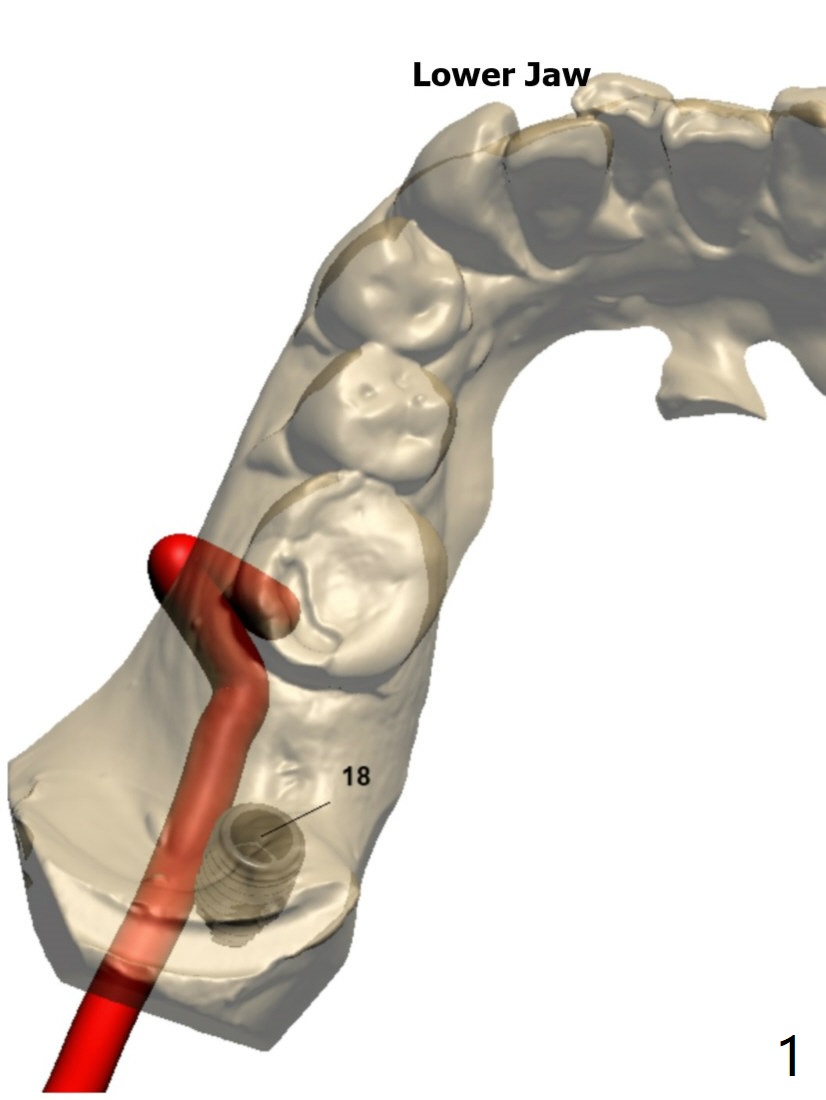

Limited Mouth Opening

Before surgery, measure the interincisal edge distance. It should be 45 mm to have smooth surgery. Call the patient whether she has taken measures to reduce the trismus (night guard and muscle relaxant).